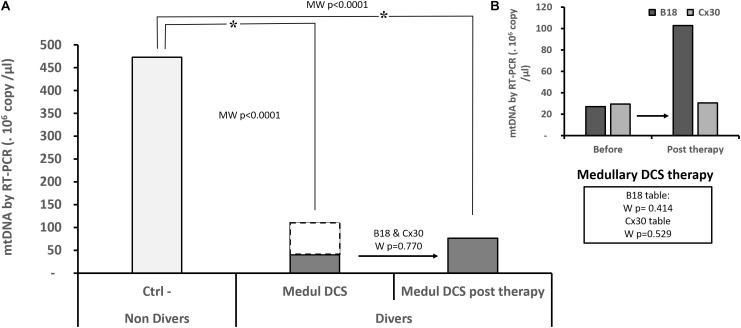

Effect of Hyperbaric Oxygen

In the context of their continuity of care, 26 patients were sampled. This made it possible to quantify the circulating mtDNA just after their treatment table. Out of 22 Medullary DCS, 14 were treated with the B18 table and 8 with the modified Comex 30 table (Cx30). The 2 Cerebro DCS, like the 2 Vestib DCS, were each treated with a different table. Only the Medullary DCS were analyzed for homogeneity reasons. The Ctrl– experienced an A15 air table.

The hyperoxic hyperbaric treatments were either of the B18 type (150 min, maximum pressure 2.8 ATA, 370 OTU, 235% CNS toxicity), or the modified Comex 30 type (330 min, maximum pressure 4.0 ATA, 792 OTU, 555% CNS toxicity), or the A15 type (50 min, maximum pressure 2.5 ATA, 166 OTU, 112% CNS toxicity). The B18 and Cx30 tables experience air or pure oxygen intermittently, with in addition a Nitrox 50 mixture from the start for the modified Comex 30 table. The Comex 30 table is usually reserved for the most severely afflicted patients.

More specifically concerning the Medullary DCS whom it has been possible to follow-up (Figure 3), their level of mtDNA remains significantly different from the Ctrl- subjects who have not dived (KWCtrl-/MedulDCS/MedulDCSpost-therapy, p < 0.0001). The analysis of paired data has not made it possible to show an evolution in their DNA level after treatment, whether the tables are considered together (WB18andCx30, n = 22, p = 0.770) or separately (WB18, n = 14, p = 0.414; WCx30, n = 8, p = 0.529).

FIGURE 3.

Quantity of circulating mitochondrial DNA in the patients suffering from medullary DCS (A), before and after treatment by B18 (n = 14) or Cx30 (n = 8) (B). Only Medullary DCS patients with values before and after treatment are compared to the non-diving subject (Ctrl-, n = 22): the dots represent the totality of medullary DCS patients (n = 57) (A). Asterisk (∗) means that the statistical difference is significant. KW p < 0.0001 post hoc Conover-Iman with a corrected significance level (Bonferroni) of 0.0167. NS shows an absence of statistic difference for the paired samples (Wilcoxon test: W).